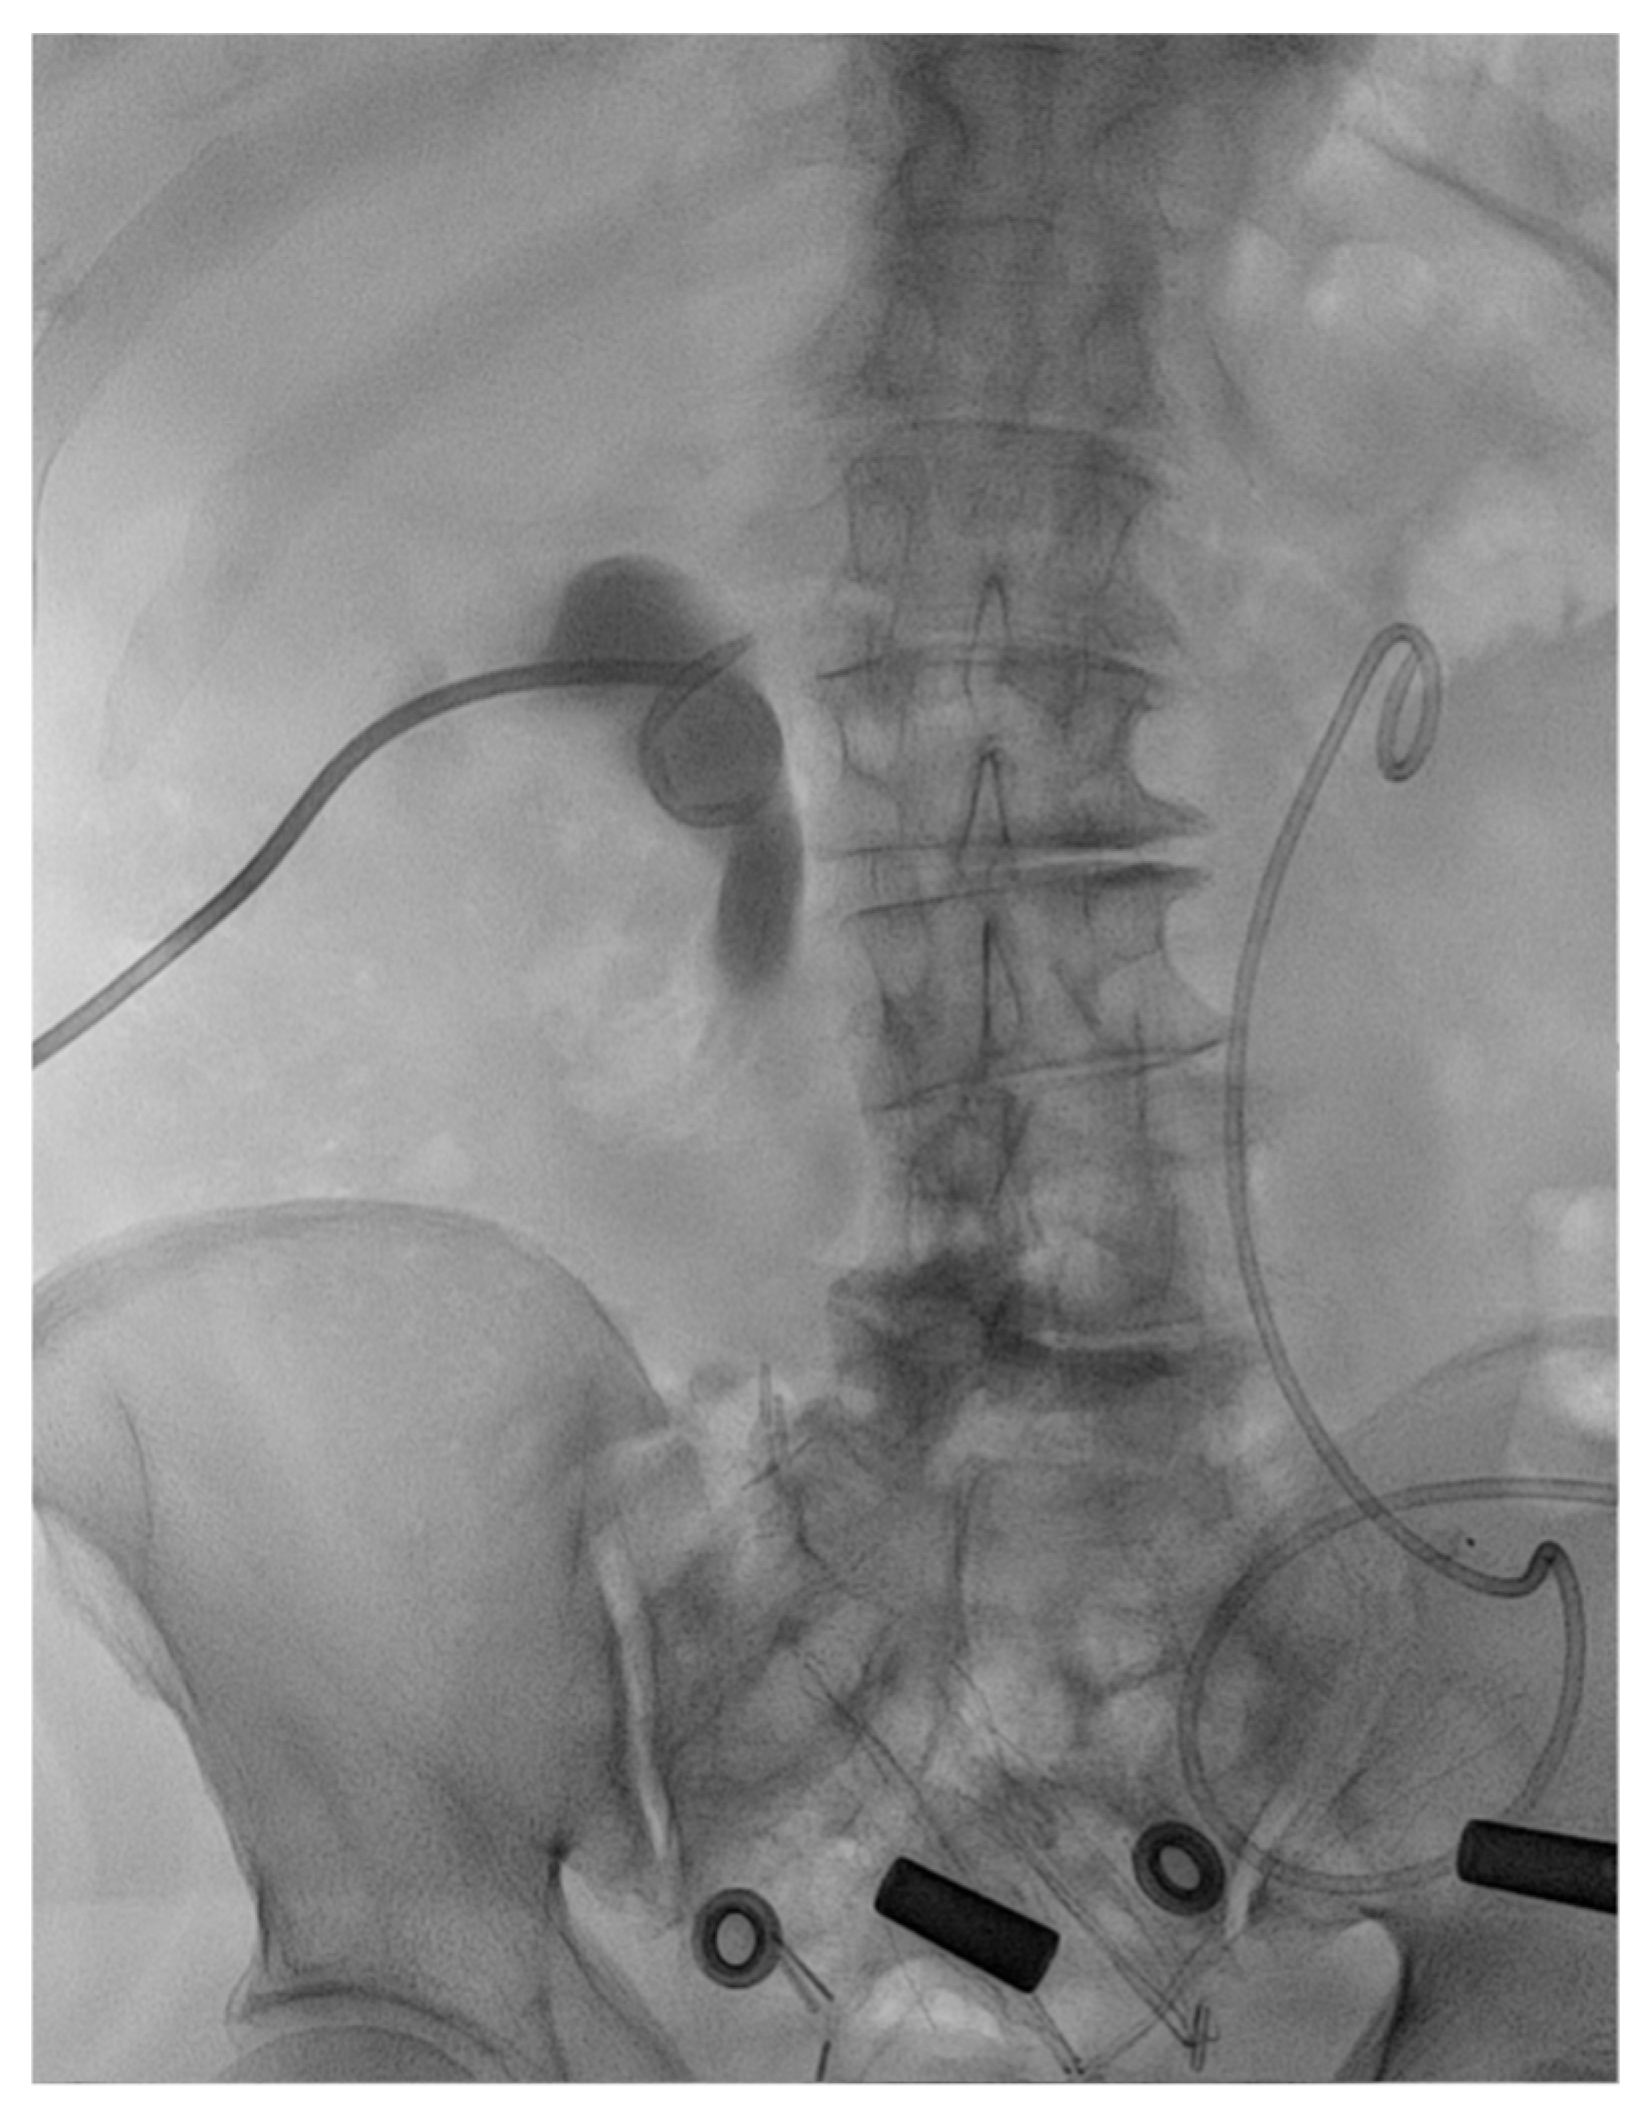

2. Case Presentation

2.2. Treatment

2.3. Outcome and Follow-Up